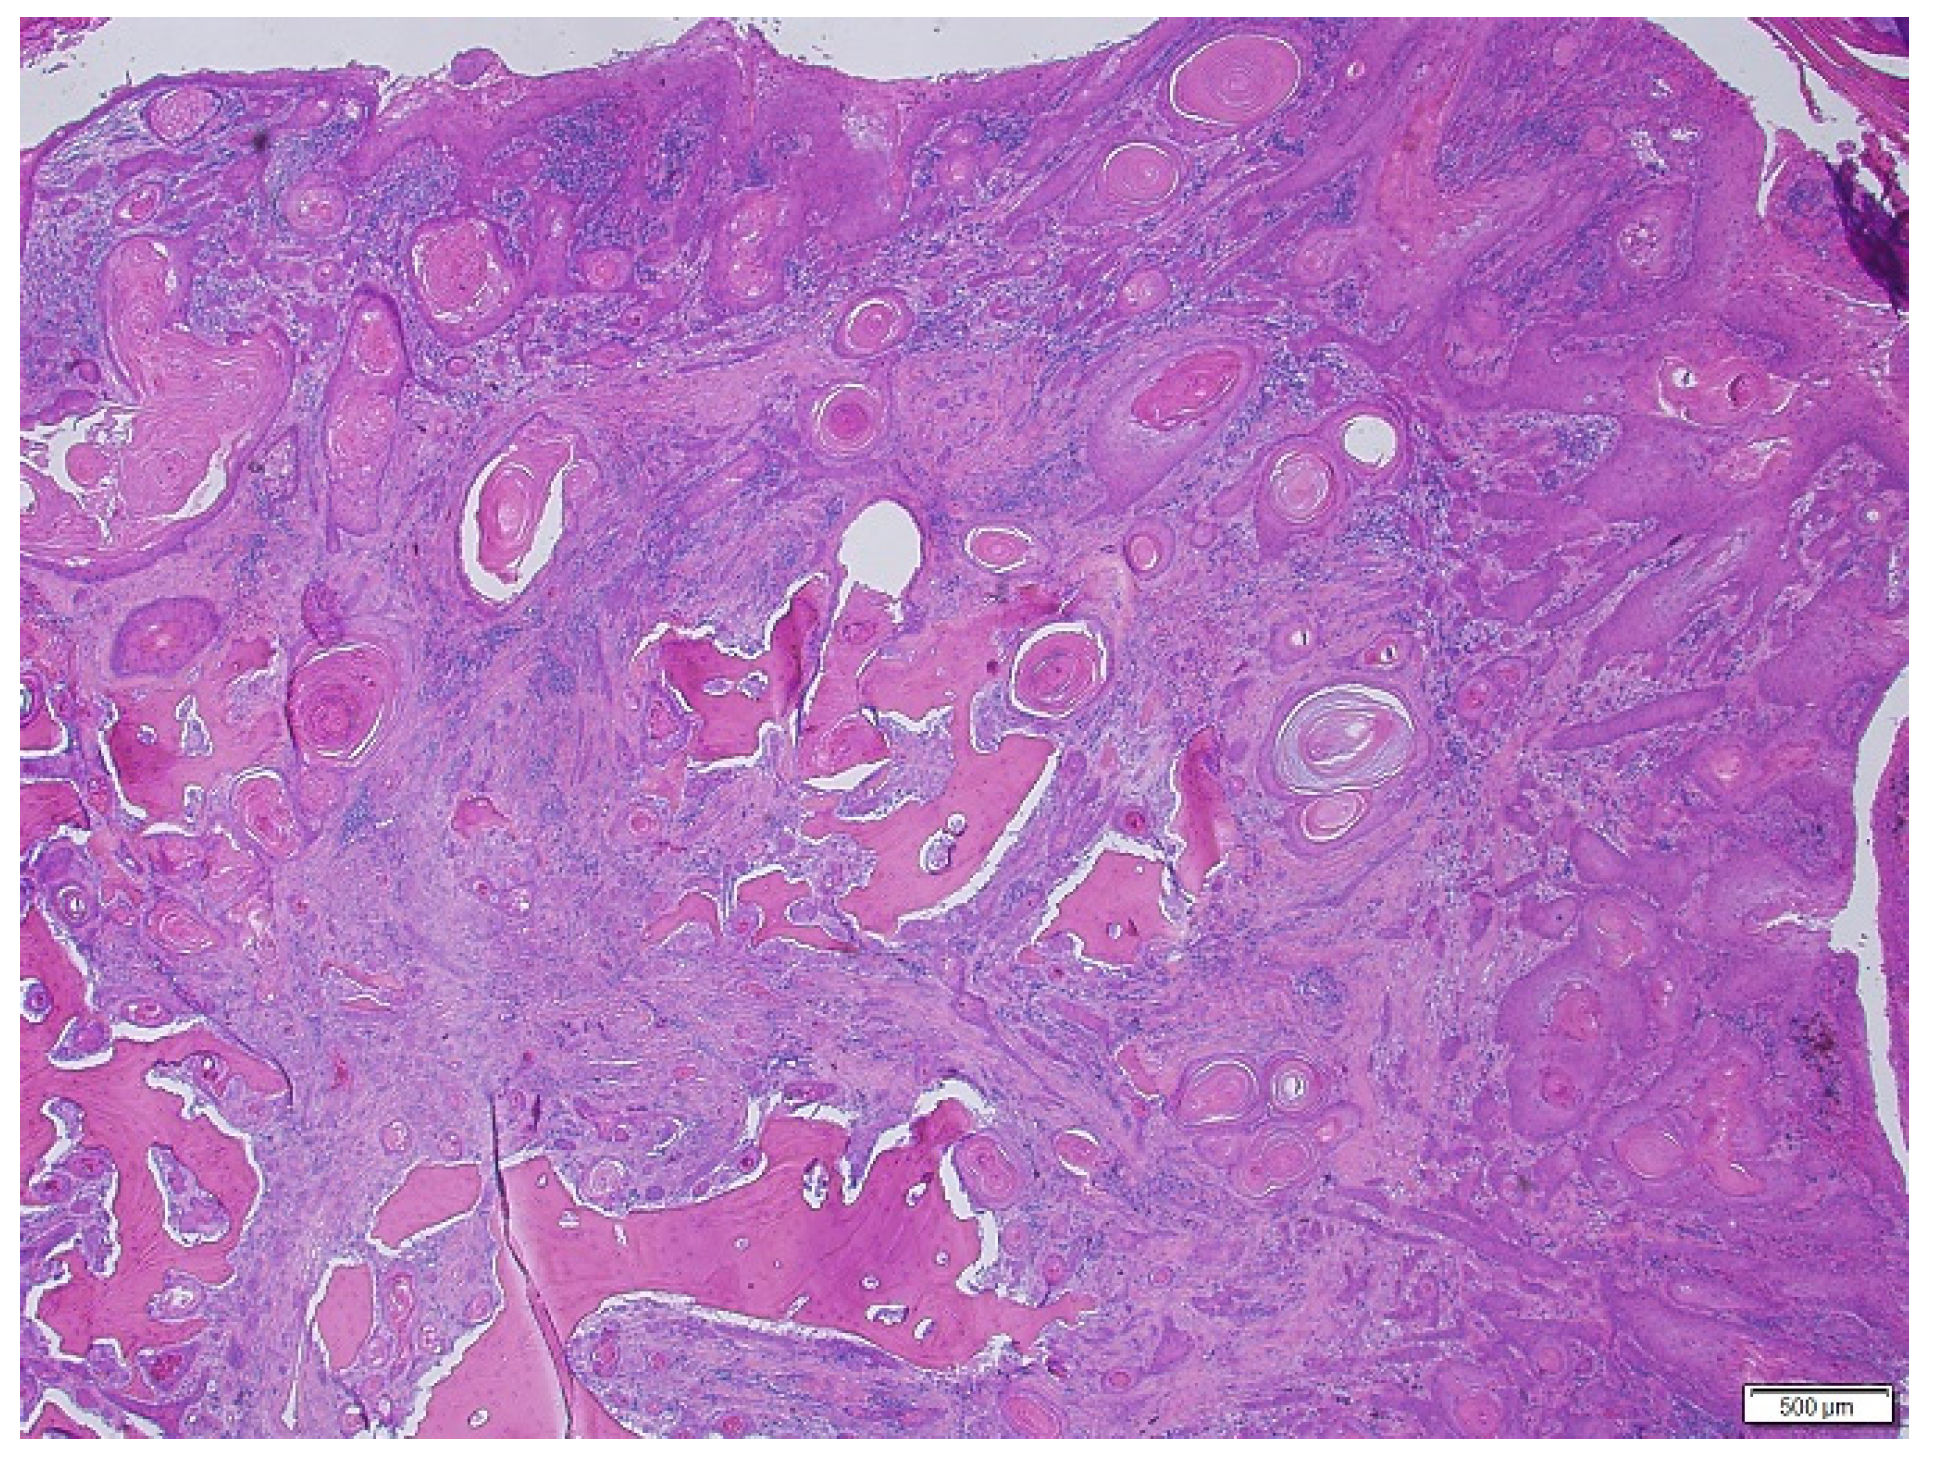

2.4. Histopathology

3. Results